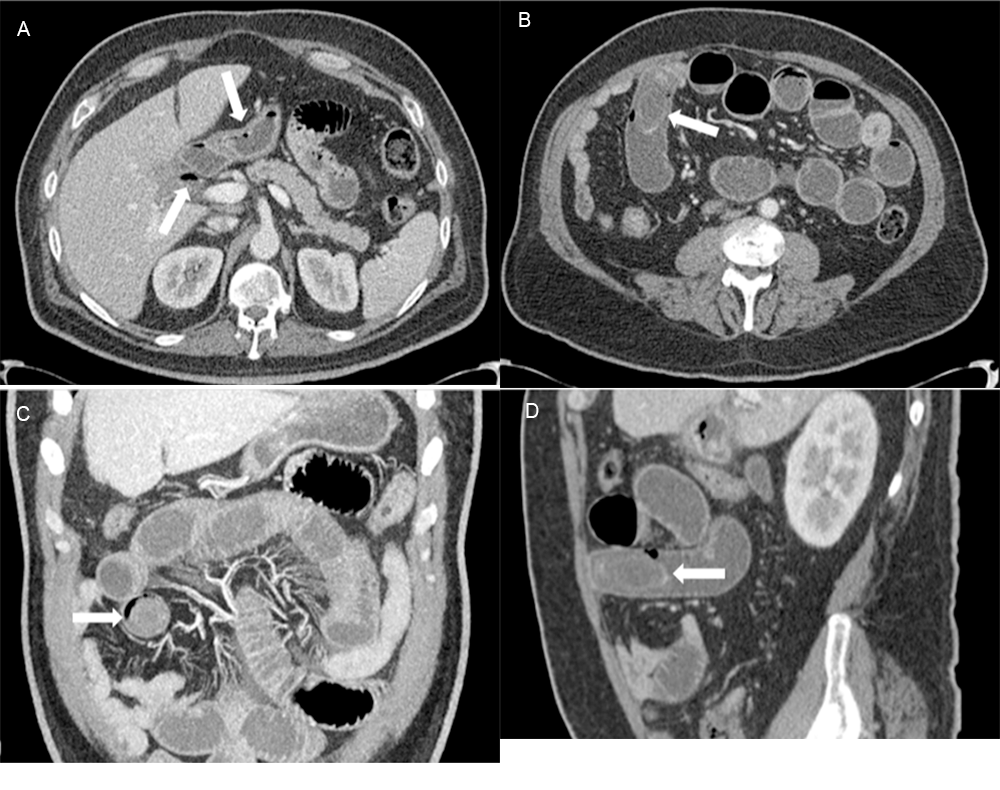

On physical examination, the patient was afebrile and in mild distress. His abdomen was distended, diffusely tender to palpation, and worse in the right upper and lower quadrants without rebound tenderness. Laboratory studies revealed a white cell count of 14,600 per microliter. The remainder of the laboratory studies were within normal limits. Computed tomography (CT) demonstrated evidence of a perforated gallbladder with an air-fluid track extending to the duodenal bulb/gastric antrum (Figure 1A). A large mass was visualized within the small bowel in the right lower quadrant, consistent with an ectopic gallstone, with associated high-grade obstruction and pneumobilia (Rigler's triad) (Figure 1B [axial], Figure 1C [coronal], and Figure 1D [sagittal]).

Figure 1. CT Scans of Perforated Gallbladder. Published With Permission

A) Perforated gallbladder with air-fluid track extending to duodenal bulb/gastric antrum. B) Axial view; C) coronal view; and D) sagittal view of gallstone.

The presentation of the patient was compatible with an acute bowel obstruction, warranting a CT. CT has been demonstrated to be superior to plain abdominal films or ultrasound in diagnosing gallstone ileus.¹⁵ Findings on the first look from CT imaging included intussusception as a possible differential due to similarities in the imaging characteristics (Figure 3). The final radiologist report declared a perforated gallbladder with an air-fluid track extending to the duodenal bulb/gastric antrum. The diagnosis of gallstone ileus was most compatible with the patient's diagnostic imaging, as most fistulas occur between the gallbladder and the duodenum due to their proximity.⁹⁻¹¹

On CT imaging, the approximate size of the gallstone was 4.2 × 2.5 cm. It was located within the lumen of the small bowel in the right lower quadrant with associated proximal bowel dilation and pneumobilia. This was consistent with the characteristic Rigler's triad (1. pneumobilia; 2. small bowel obstruction; 3. ectopic gallstone), a radiologic finding leading to the diagnosis of gallstone ileus.¹⁶